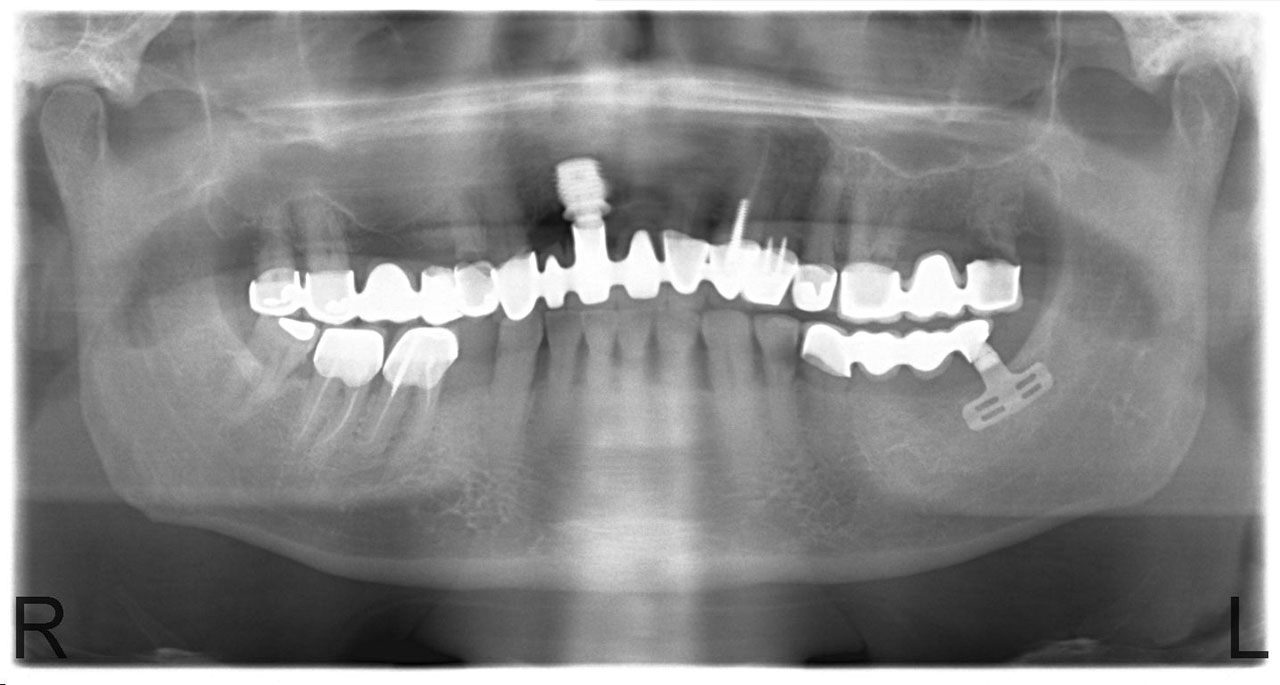

• esettanulmany-04

Impantáció előtt, súlyos fogágy pusztulás, gyulladás látható.